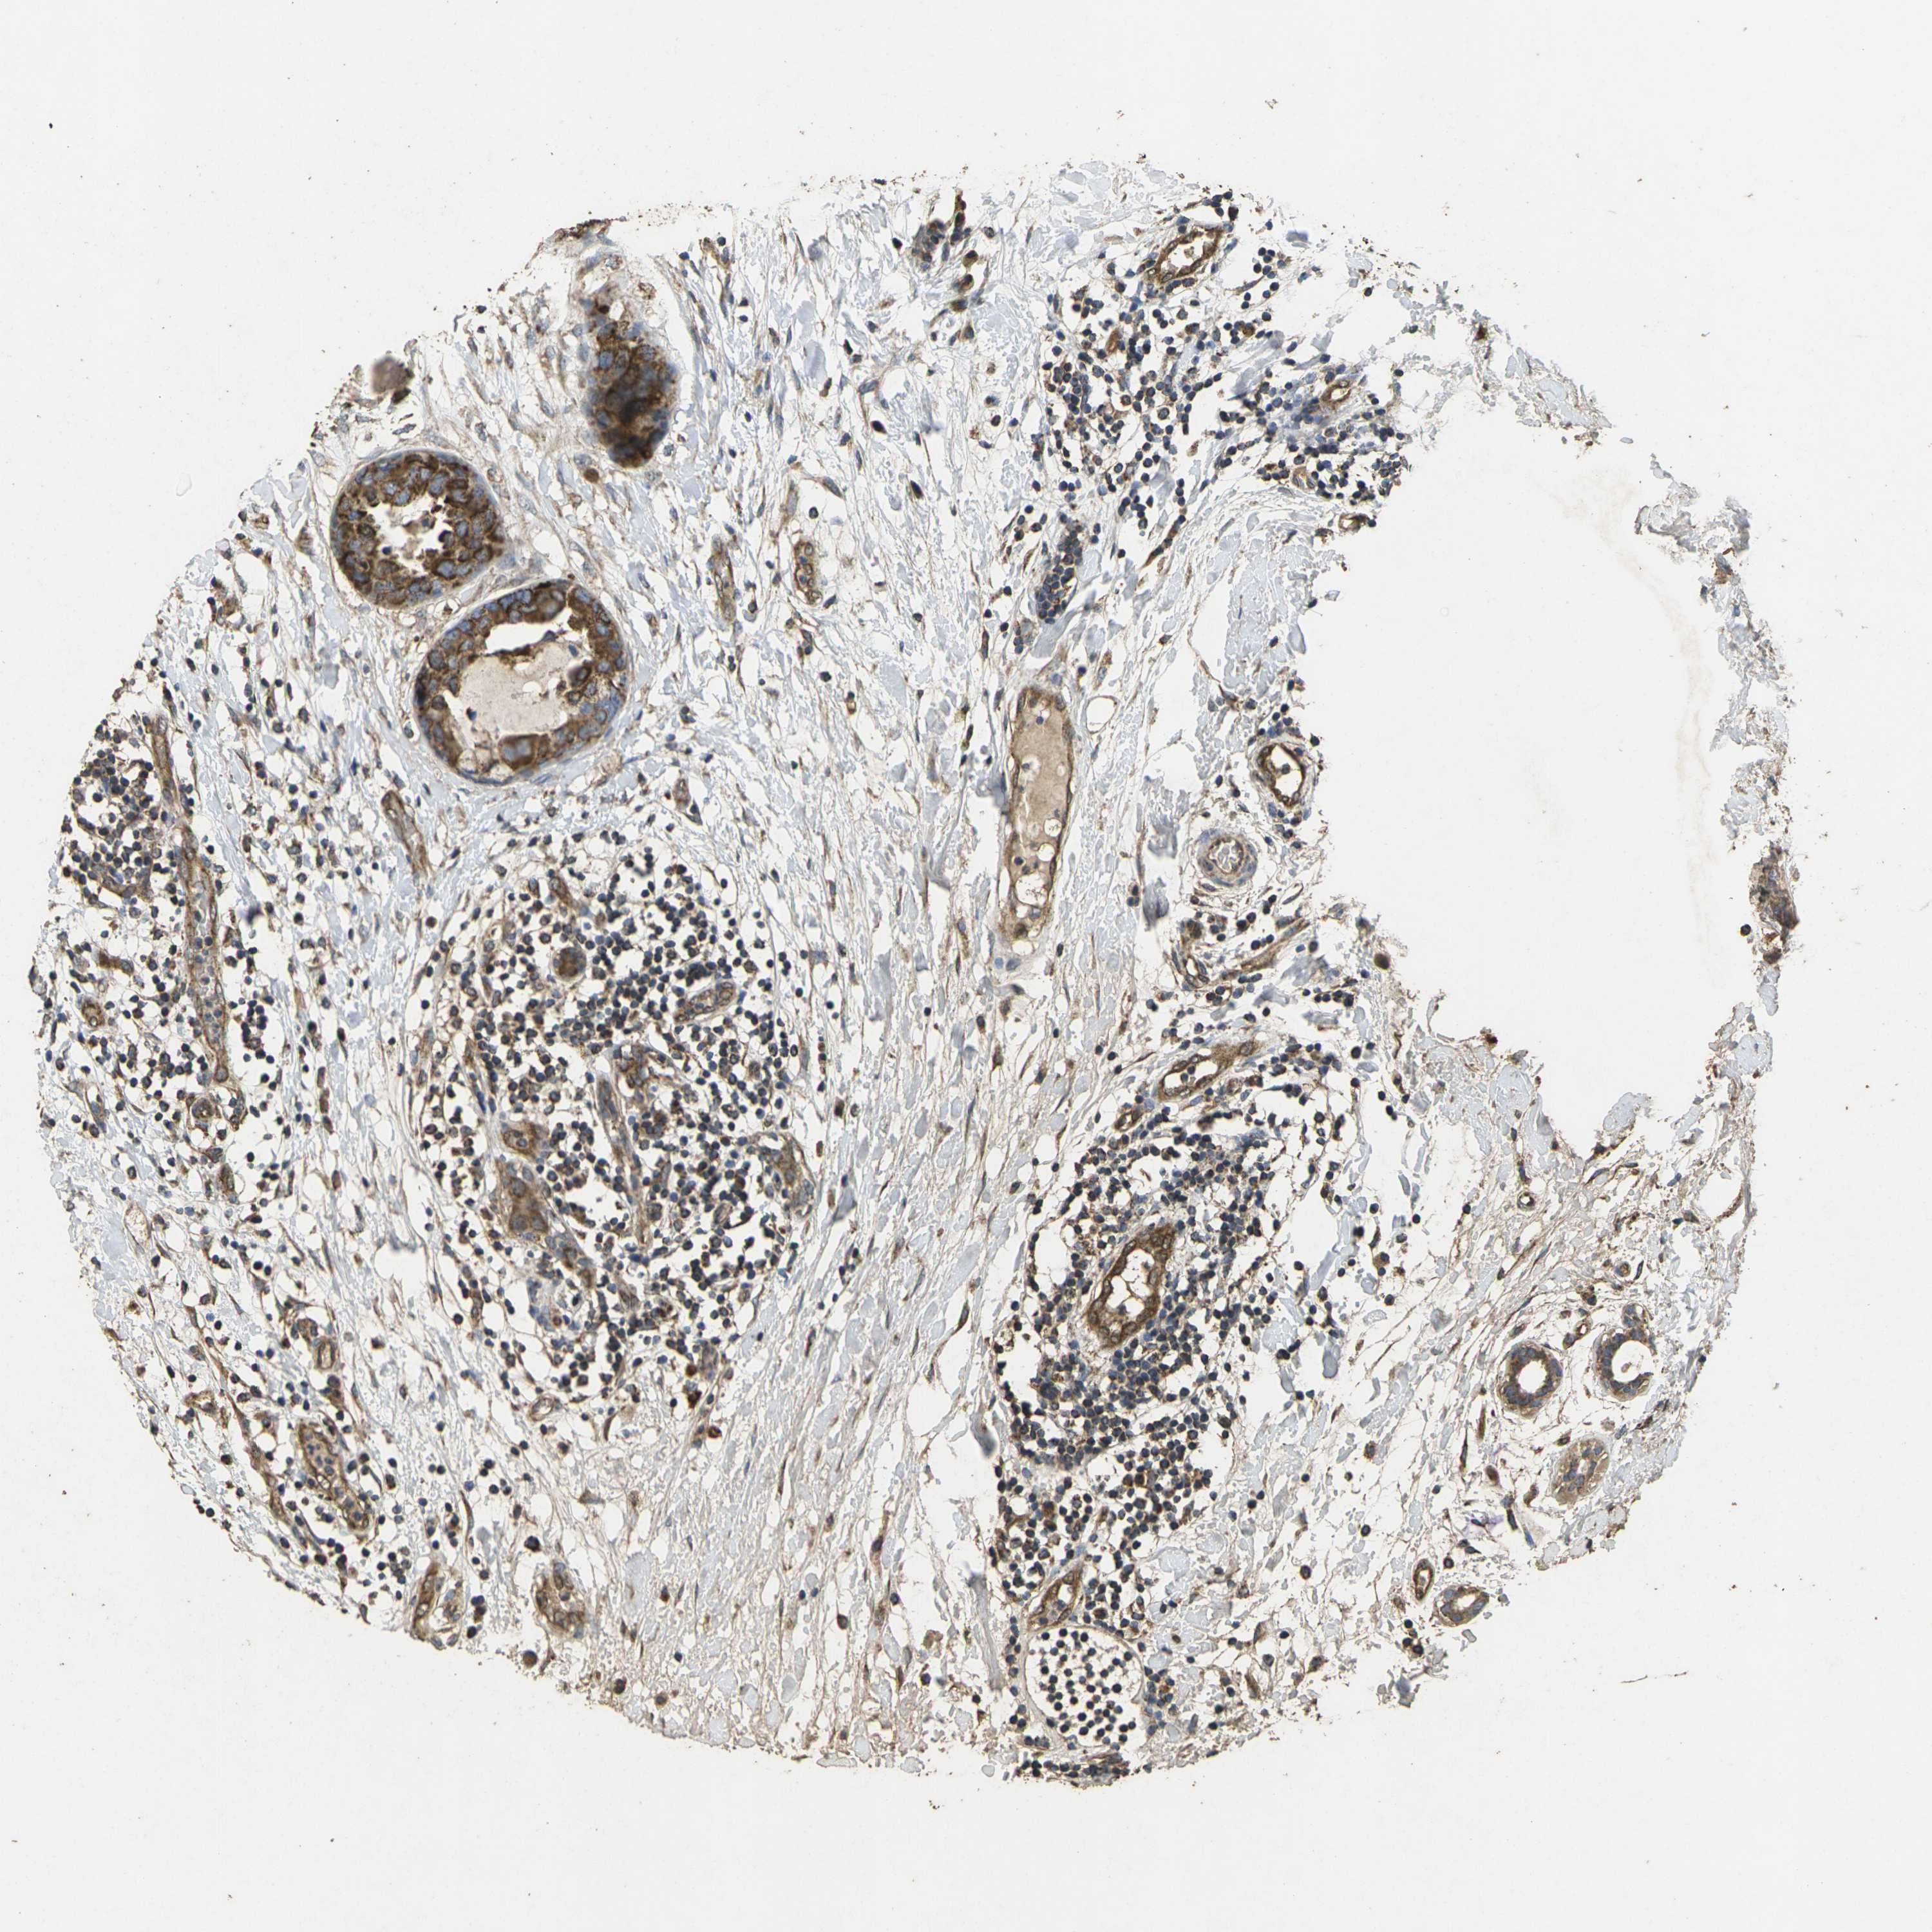

CANCER BREAST CANCER Show tissue menu

BRCA TCGA BRCA VALIDATION PROTEIN EXPRESSION

ANTIBODIES

AND

VALIDATION